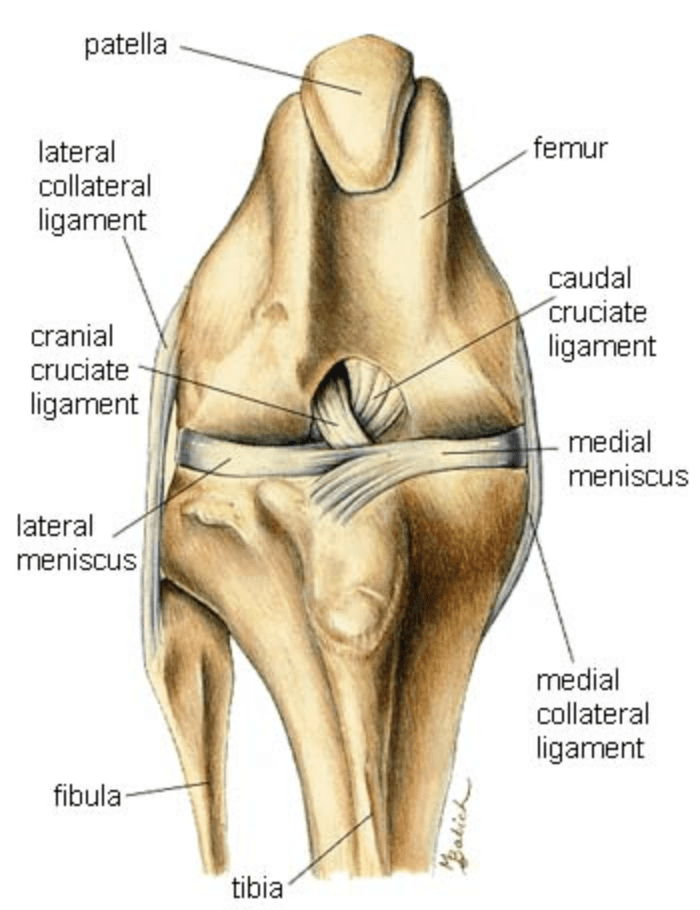

The Cranial Cruciate Ligament (CrCL) is equivalent to the Anterior Cruciate Ligament (ACL) in humans.

It plays a vital role in stabilizing the knee by preventing the tibia from moving forward relative to the femur, limiting internal rotation, and preventing hyperextension of the knee.

On exam, the veterinarian looks for abnormal forward movement of the tibia relative to the femur (known as cranial drawer or tibial thrust), which confirms damage to the ligament.